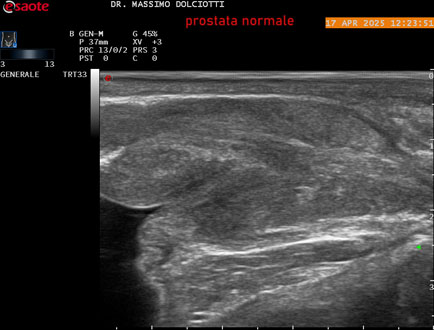

Ecografia del: 17/04/2025

Strumento: Esaote MyLab Eight

Sonda: Convex Multifrequenza 1-8 MHz, Endocavitaria Multifrequenza 3-9 MHz e 3-13 MHz

Età Paziente: M 35 anni

Motivazione dell'esame: disuria.

Commento all'esame: le immagini ed il video documentano la prostata di ecostruttura regolare e morfovolumetria normale con diametro trasversale di 40 mm, diametro anteroposteriore di 21 mm e diametro longitudinale di 43 mm, con volume prostatico calcolato di 18 cc (v.n. < 20 cc), il profilo prostatico è regolare e netto, non si documentano calcificazioni intraghiandolari, la vascolarizzazione della ghiandola è normale. La vescicola seminale destra presenta diametro longitudinale di 44,4 x 7,8 mm, la vescicale seminale sinistra ha diametro longitudinale di 45,3 mm x 7,2 mm.

Conclusioni: prostata normale (normal prostate).